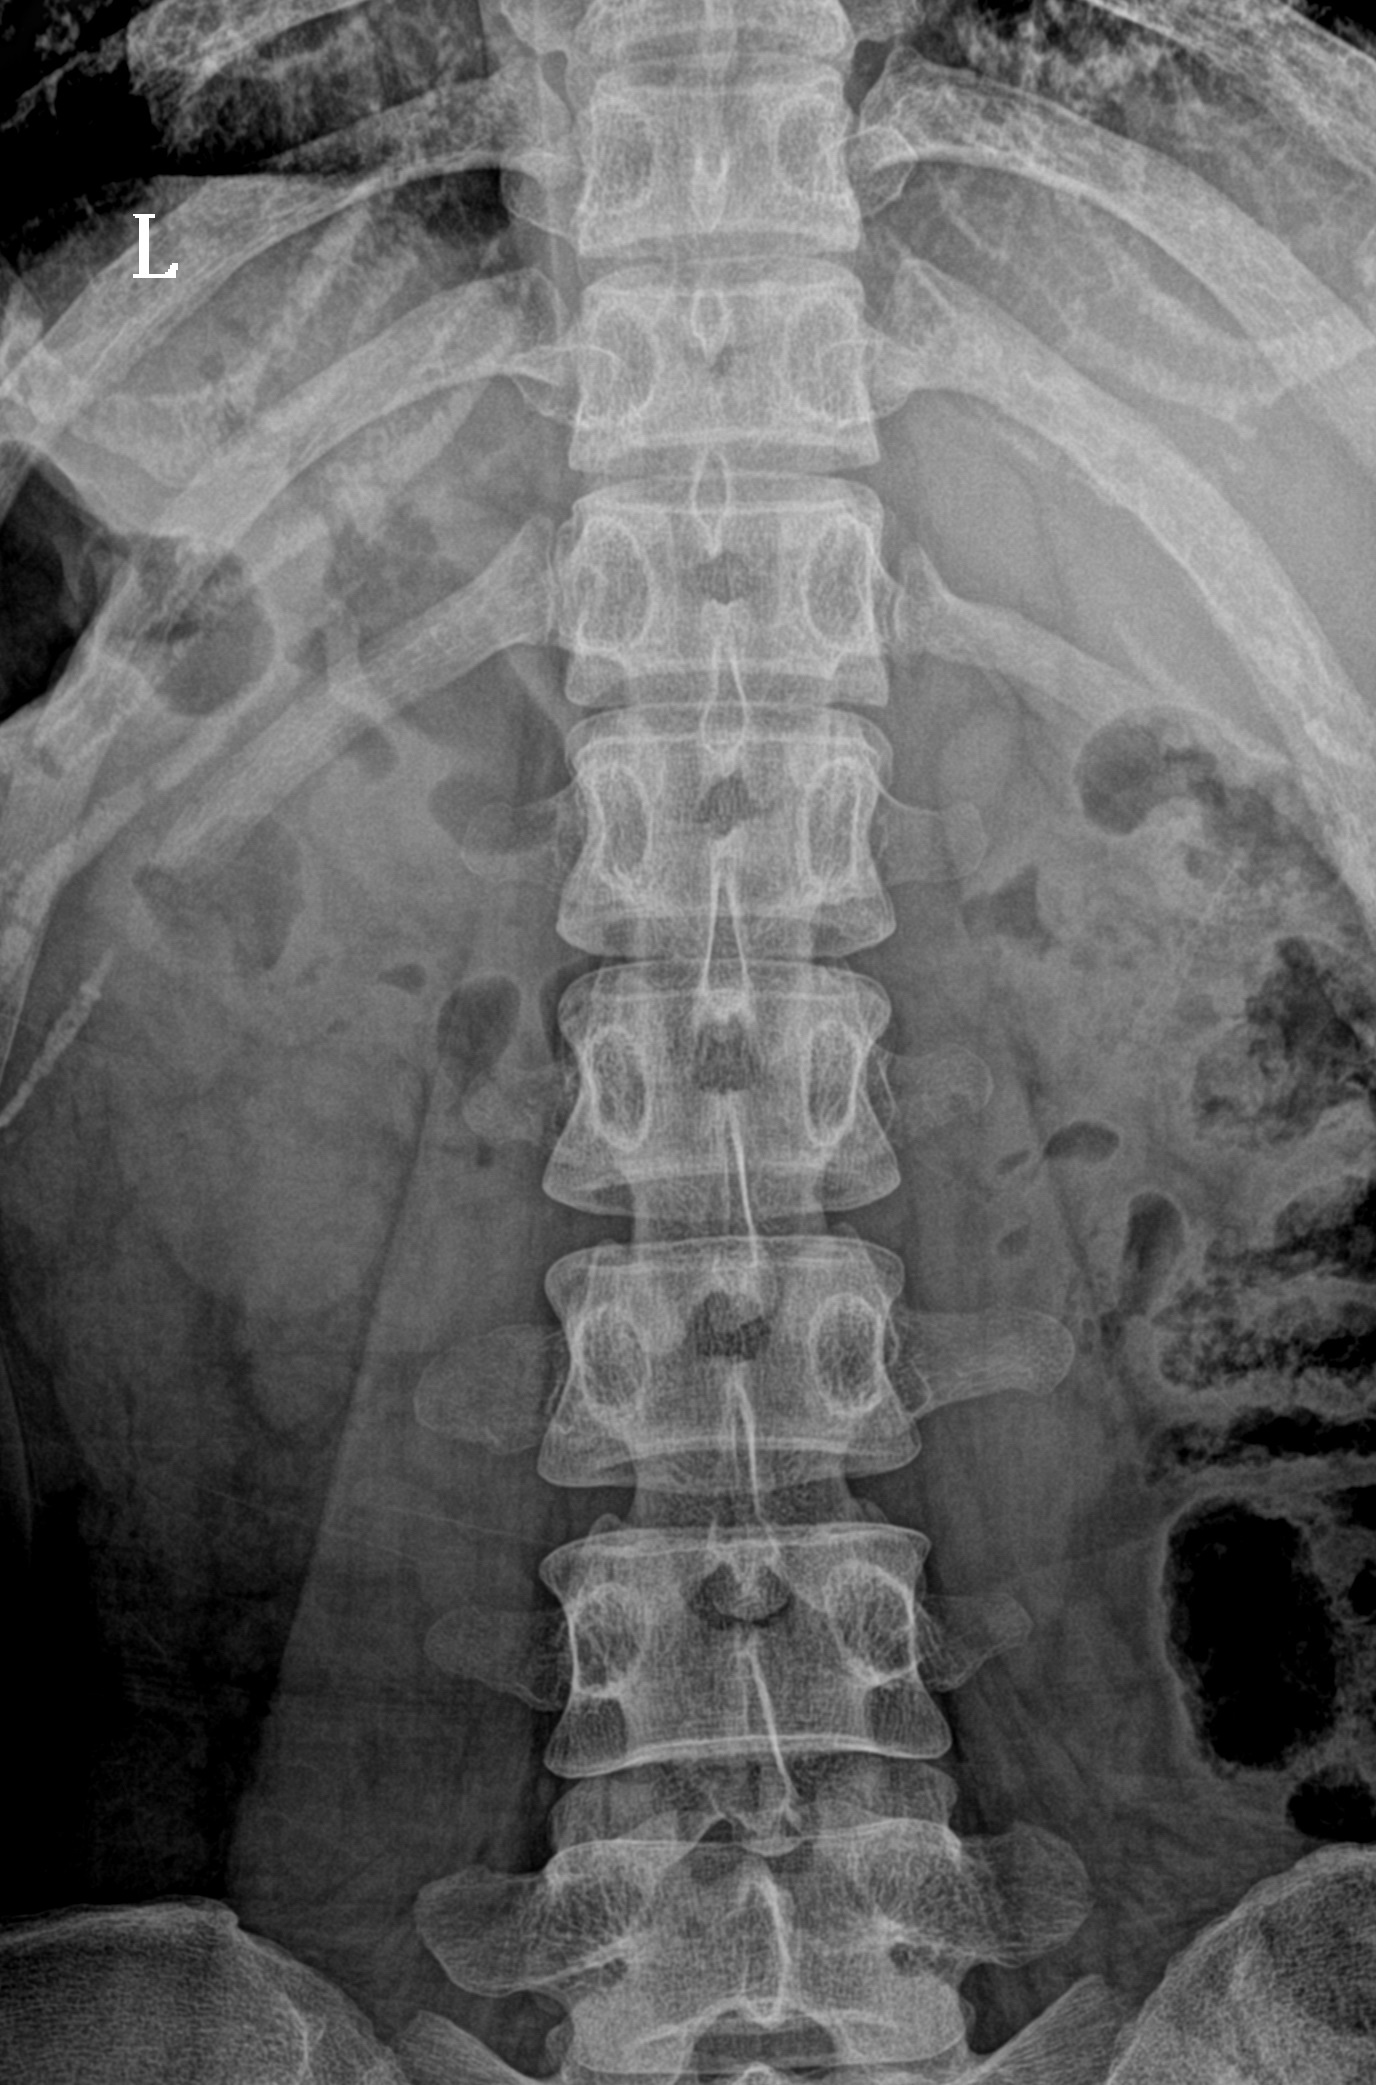

采用17x17英寸無(wú)線大平板,整板無(wú)拼接,圖像視野寬闊,成像清晰細(xì)膩。